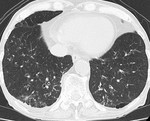

[画像メモ]胃癌、リンパ節転移(N因子)のCT診断について 2011-05-27